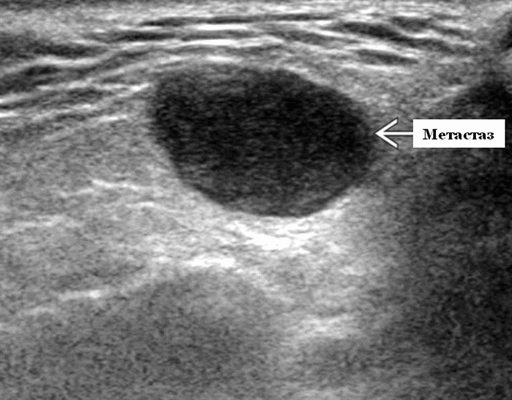

Серошкальное УЗИ. Узловая НХЛ. Одиночные или множественные увеличенные яйцевидные внутрипаротидные лимфатические узлы. Гомогенно гипоэхогенный по отношению к паренхиме околоушной железы. Сетчатый эхосигнал. Заднее акустическое усиление. Первичная паренхиматозная НХЛ. Рассеянный, неоднородный эхосигнал; нечеткие, гипоэхогенные, похожие на опухоль участки. В пунктате внутрикистозная или паренхиматозная кальцификация из-за конечной стадии воспалительного изменения. Небольшие кистозные области образуются из-за сдавления терминальных протоков лимфоидной гипертрофией. Множественные небольшие гипоэхогенные участки (представляют собой лимфоидные агрегаты), разбросанные на фоне ткани слюнной железы. Изменения могут имитировать хронический сиалоаденит и диагноз часто ставится при биопсии. На УЗИ необходимо искать аналогичное поражение других слюнных и слезных желез, фон синдром Шегрена, BLEL. Может иметь или не иметь перипаротидную и шейную лимфаденопатию

- Узловая неходжкинская лимфома (НХЛ): одиночные или множественные увеличенные яйцевидные внутрипаротидные лимфатические узлы, которые на УЗИ гомогенно гипоэхогенны по отношению к паренхиме околоушной железы, эхо-картина сетчатая. Заднее акустическое усиление. Выраженная внутриузловая гиперваскуляризация